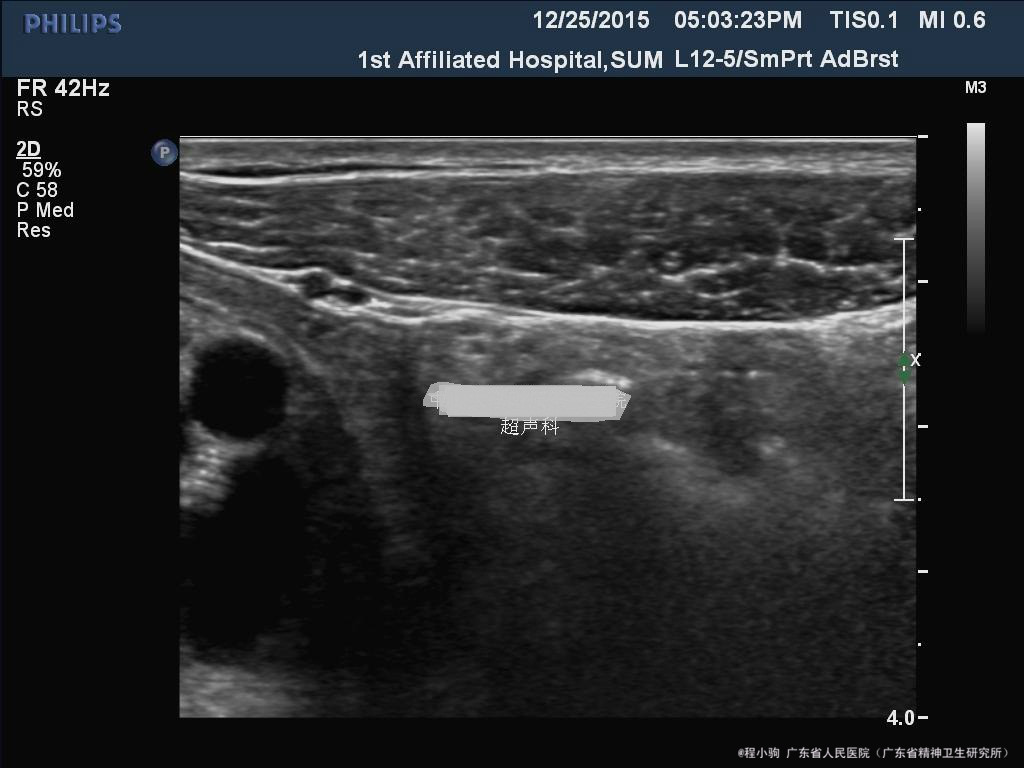

2.腹部B超;阑尾横切面呈靶形,直径8cm,较僵硬。